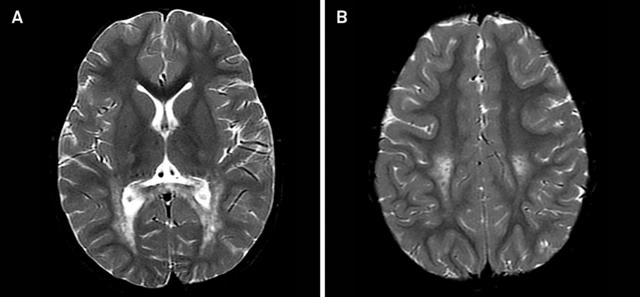

图 5 A~B:T2WI 可见双侧半卵圆中心至内囊后肢的皮质脊髓束对称性高信号,胼胝体压部亦有受累

图 6 FLAIR / T2WI 提示脑白质病变,累及锥体束